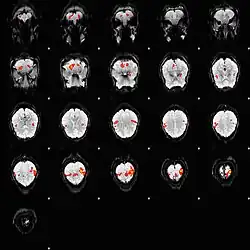

L'imagerie par résonance magnétique fonctionnelle repose sur la mesure du signal BOLD.

Le signal BOLD (de l'anglais blood-oxygen-level dependent, « dépendant du niveau d'oxygène sanguin ») est le signal qui reflète les variations locales et transitoires de la quantité d'oxygène transporté par l'hémoglobine en fonction de l'activité neuronale du cerveau[1].